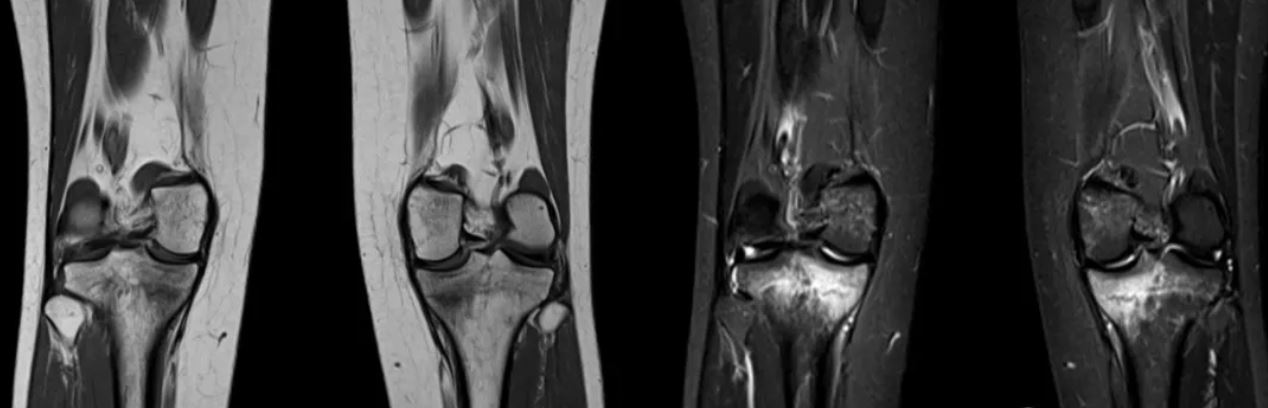

女,20岁,长期没有活动的情况,猛烈地参加一次长跑运动后 ,主诉出现双侧内侧胫骨疼痛。在双侧胫骨中,内侧近端应力性骨折是明显的。用手指一按压膝关节内侧平台明显压痛! MRI提示双膝关节内侧胫骨平台骨水肿(骨挫伤)